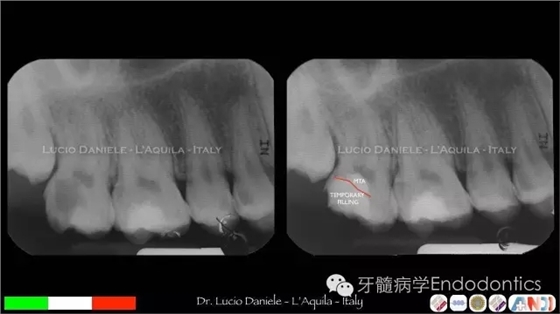

圖9.

圖10.